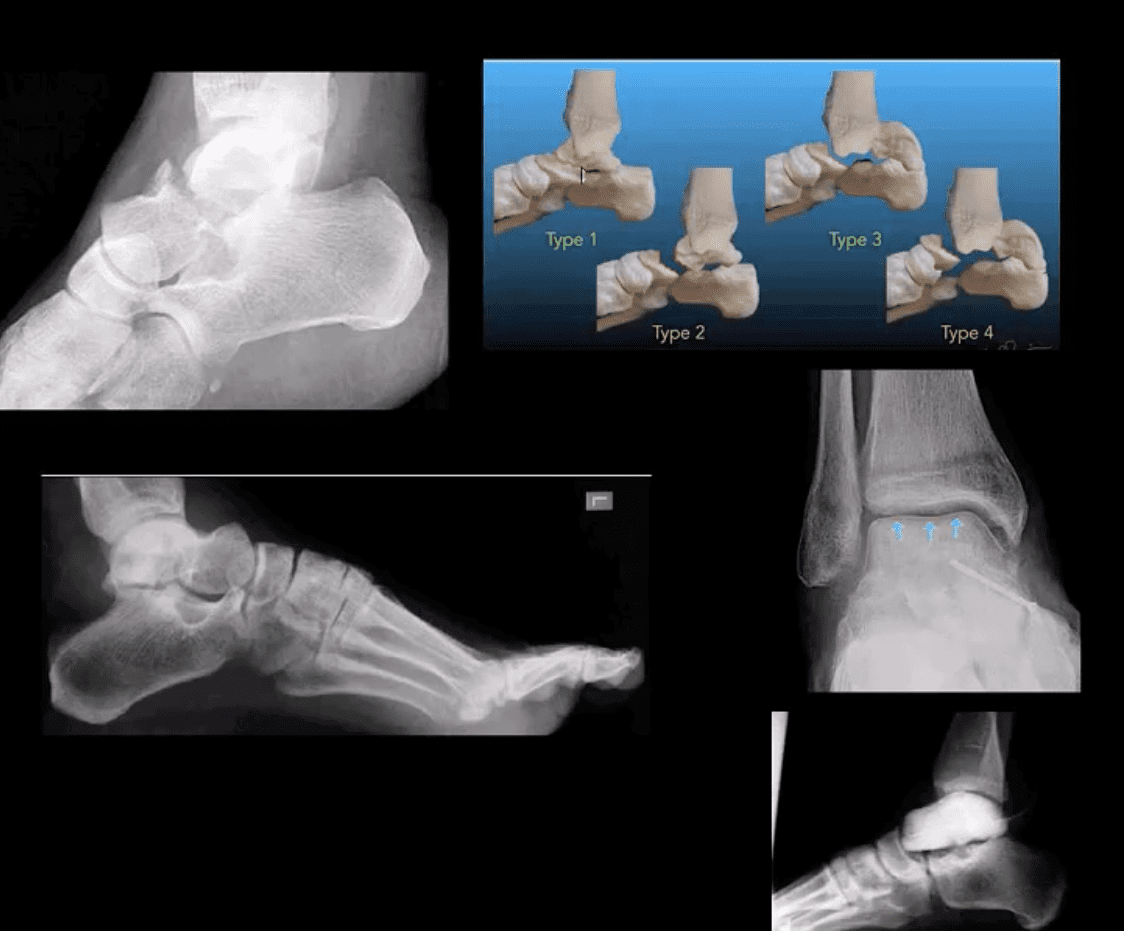

Tarsal Bones

- M/C fractured tarsal bone is the Talus. M/C region: talar neck (30-50%). Mechanism: Axial loading in dorsiflexion. Complications: Ischemic osteonecrosis (AVN) of the talus. Premature (2nd OA). Imaging: 1st step: radiographs, CT can be helpful with further delineation

- Hawkins classification helps with Dx, prognosis & treatment. “Hawkins sign’ on plain film/CT scan may help with AVN Dx. (above blue arrows indicate good prognosis d/t radioluncent line indicating no AVN because bone is vascularized and hence resorbed)

- Rx: Type 1: conservative with short leg cast or boot (risk of AVN-0-15%), Type 2-4-ORIF (risk of AVN 50%-100%)